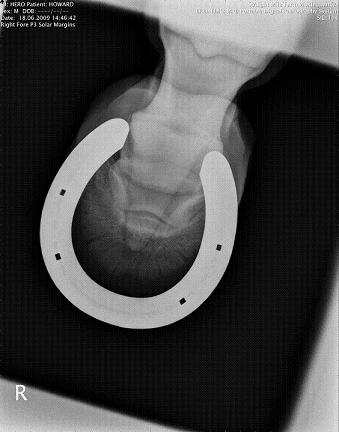

RF P3 solar margins

1) I believe your veterinarian is saying poor foot balance has put extra stress on the coffin bone as demonstrated by the changes in the tip he describes. He believes that balancing the foot and relieving break over and reduced exercise the horse in time will come sound for full work again. I have to ask did he also do a posterior digital block prior to the ab. ses. block?

3) I cannot count how many horses with both diagnosed and undiagnosed lameness of the foot that were remarkably more sound with proper balancing, squaring off of the toe, and rockering the bottom of the foot or shoe. The LF lateral above suggests to me there is a fair about of horn out in front of the coffin bone to deal with. Maybe instead of you talking to the vet you need to put the vet in touch with the farrier.

Secondly i did not mention that the xrays taken on the 18/06/09 show him with a long toe, however i neglected to mention he was a week away from being due shoes.

He has been shod today, with Natural balance on all 4 feet. The farrier feels he cannot take the toe any further back.

Compared to the radiographs, it looks like he found a fair amount of toe to remove, good for him. Assuming as low as possible with as small a dose as possible principles were used, the improvement with the PDN then sound with AbSes is further support for tagging this at the tip of the toe or somewhere along a line between the tip and the coffin jt.